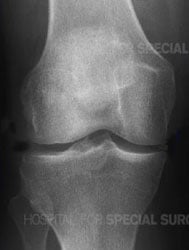

X-ray of a healthy knee joint

Knee arthritis literally means "inflammation of the knee joint," although inflammation is not always present when there is arthritis. On an X-ray of a knee with arthritis, the space between the upper and lower bones is often reduced or, in some places, even absent due to loss of cartilage, the shiny material which covers the ends of the bones.

X-rays are very helpful in diagnosing advanced knee osteoarthritis because the joint will have specific characteristics, including:

- Bones that are closer to each other than they should be: As cartilage wears away, the joint space between them often narrows.

- Cysts: As the body responds to cartilage destruction and attempts to stabilize the joint, cysts or fluid-filled cavities can form in the bone.

- Increased bone density or uneven joints: When bones are no longer cushioned by cartilage, they can rub against one another, creating friction. The body responds by producing more bone tissue, which increases bone density. Increased bone creates uneven joint surfaces and bone spurs at the joint.